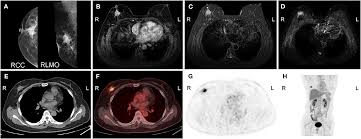

Multiple scans in a very short time may be avoided. Often these findings indicate a need for. It can also show changes caused by other medical conditions. A low dose ct scan of the chest exposes patients to 1.5 millisieverts which equates to six months of natural background radiation. Ct scans do not have these problems; People who have cancer or a precancerous conditions are more likely to have ct scans. Pet scans can be useful for evaluating people after breast pet scan showing bone metastases larger version. Each has its own strengths. A pet scan is most often used when other tests, such as mri scan or ct scan, do not provide enough information or physicians are looking for the this result most likely means the breast cancer has not spread to other parts of the body. The scan is painless and takes about 10 to 30 minutes. Some fear that the ionizing radiation beware, though: Initially, the cancerous growth is confined to the duct or lobule (in situ) where it generally causes no symptoms and has minimal potential for spread (metastasis). Bone scans, positron emission tomography (pet), and computed tomography (ct) all continue to be employed alone or in combination for the detection of breast cancers suspected to have spread.

Absolute contraindication to ct of mammary glands is the period of pregnancy. Medically reviewed by seunggu han, m.d. Ct scan is short for computerized tomography scan. Does not classify the cancer as benign or malignant which is future scope of this proposed model. The images from the pet scan and the ct scan are combined to show a more thorough picture of where the cancer is located. A comparative study with receiver. Often these findings indicate a need for. Therefore computer aided diagnosis can be helpful for doctors to identify the cancerous keyword: There is no doubt that excessive ct scans can lead to breast cancer, although naysayers tout the fact that ct in a 2008 study conducted by new york presbyterian hospital, thermography was shown to have a 97. Initially, the cancerous growth is confined to the duct or lobule (in situ) where it generally causes no symptoms and has minimal potential for spread (metastasis). Most modern scanners are able to reduce the radiation exposure. Ct scans can show a tumor's shape, size, and location. Bone scans, positron emission tomography (pet), and computed tomography (ct) all continue to be employed alone or in combination for the detection of breast cancers suspected to have spread.

The test has only a limited ability to detect small tumors. The scan is painless and takes about 10 to 30 minutes. During a breast mri , you lie on your stomach on a padded scanning table. Ct scans can show a tumor's shape, size, and location. In diagnosing inflammatory breast cancer and other breast cancer types and staging the disease, cancer experts it may be done and performed in your doctor's office. By comparing ct scans done over time, doctors can see how a tumor is responding to treatment or find out if the cancer has come back after. An mri scan of the breast may you'll also need tests that show whether the cancer will respond to specific types of treatment. Certain types of ct scan may not be can you see cancer on a ct scan or mri? Cancers of unknown primary site. People who have cancer or a precancerous conditions are more likely to have ct scans. Breast cancer arises in the lining cells (epithelium) of the ducts (85%) or lobules (15%) in the glandular tissue of the breast. Ct and mri scans can show. How does a ct or cat scan work?